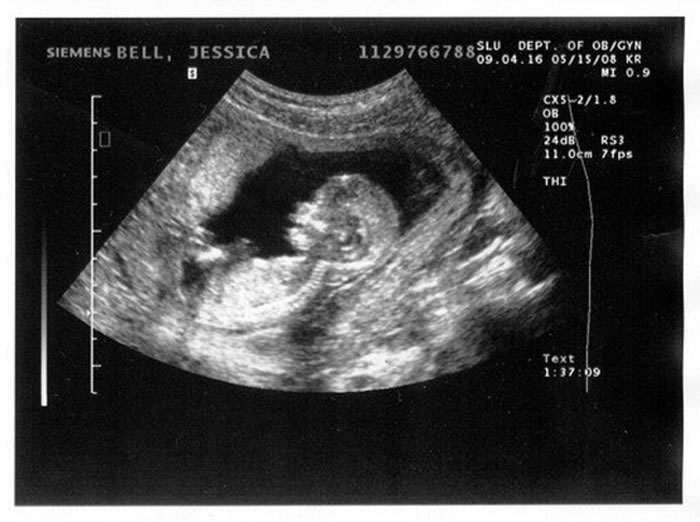

6. Визначення по УЗД

Якщо жінку цікавить, як порахувати термін вагітності в тижнях точно, потрібно довіритися медичним дослідженням і відправитися на УЗД, де можна дізнатися не тільки правильність розвитку малюка, але і дату його народження. Перше дослідження проводиться вже на 4-5 тижня, і допомагає з найбільшою точністю визначити нормативні показники, правильність розташування та термін.

Ближче до другого місяця вагітності може бути призначено ще одне дослідження, де буде виміряно зростання плоду від тім'ячка до куприка, і виявлені інші показники. Якщо, наприклад, жінка не пройшла дослідження до чотиримісячного терміну, то дата передбачуваних пологів може не відповідати датам прорахованих гінекологом по тижнях. Якщо дата не відповідає зазначеній гінекологом, тоді в картку може бути занесена наступний запис «затримка розвитку плода».

Після того, як буде проведено дослідження лікарем-узистом, можна максимально точно дізнатися термін розродження, і починати готуватися до радісної події. Варто відзначити, що найбільш точні дати визначаються на першому триместрі, подальші результати будуть не такими достовірними.